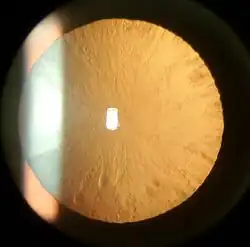

Cortical cataract of a 60-year-old male

Cortical cataract of a 60-year-old male -

Cortical cataracts are due to the lens cortex (outer layer) becoming opaque. They occur when changes in the fluid contained in the periphery of the lens cause fissuring. When these cataracts are viewed through an ophthalmoscope, or other magnification system, the appearance is similar to white spokes of a wheel. Symptoms often include problems with glare and light scatter at night.[47]